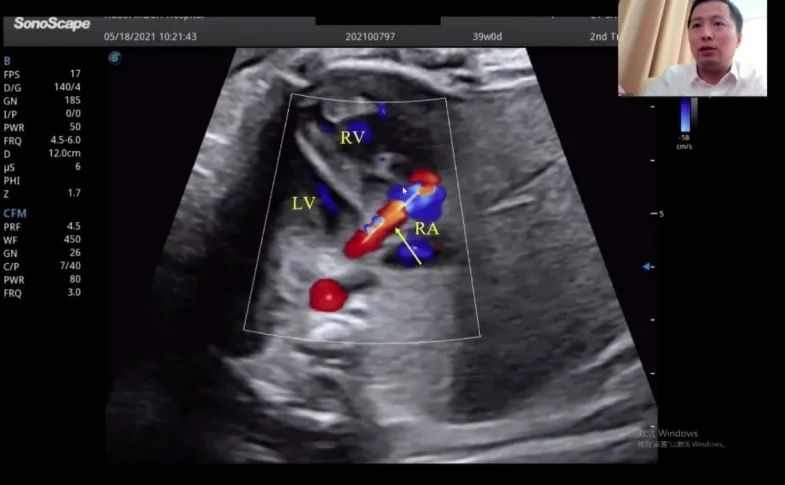

浙江大学医学院附属邵逸夫医院的赵博文教授聚焦先天性心脏疾病(CHD)的产前诊断,通过特殊病例的展示讲解,包括法洛四联症(TOF,一种常见的先天性心脏畸形)的时空关联成像技术(Spatio-Temporal Image Correlation,STIC)、大动脉完全转位(cTGA)和右心室双出口(DORV)的图像,前瞻性地提出智能胎心的应用场景。“胎心检查人工智能的应用非常有价值,能够缩短检查时间,提高临床的诊疗效率,”赵教授如是说。

湖北省妇幼保健院的赵胜教授在会上带来了胎儿冠状动脉瘘超声诊断研究的分享。赵教授表示,冠状动脉瘘在妊娠晚期可通过超声检查显示出来,经线圈栓塞或冠状动脉瘘术后,进一步的临床过程通常较为顺利。